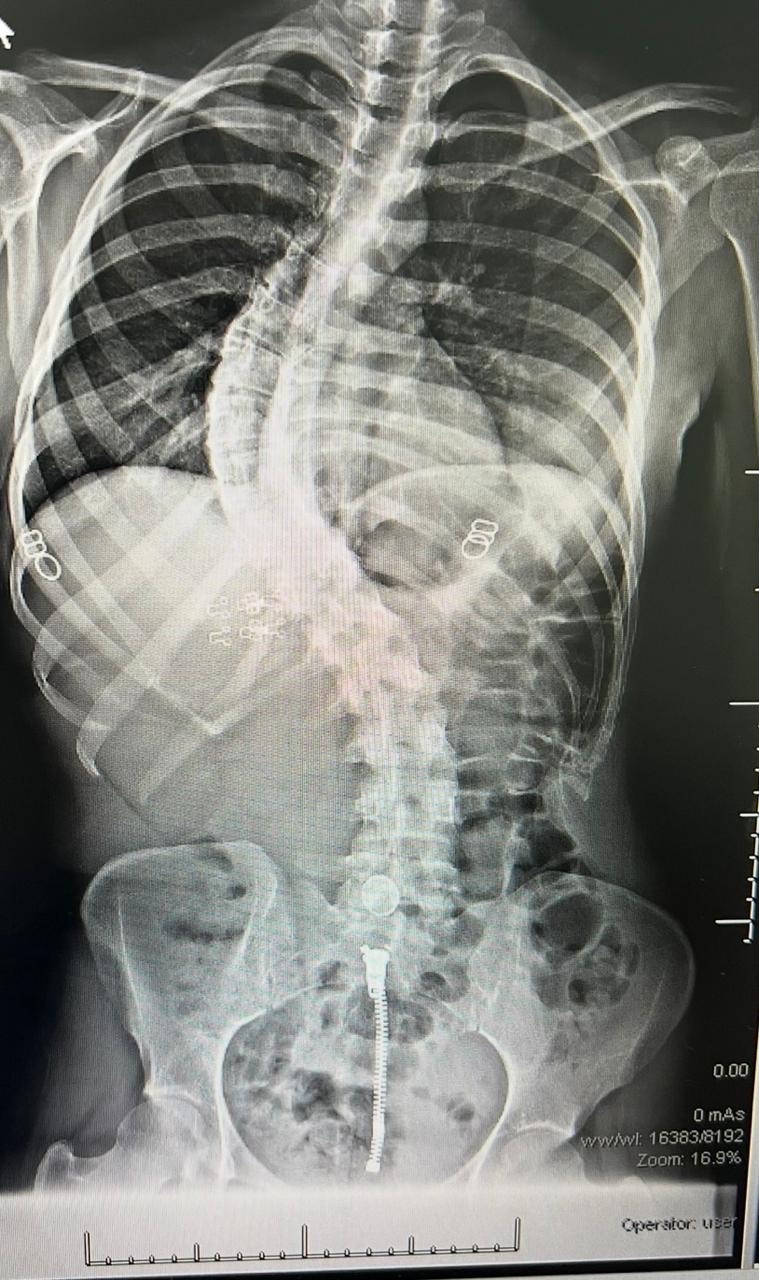

سجل مستشفى القطيف المركزي إنجازاً طبياً نوعياً بنجاح أول حالتين لتصحيح انحناء العمود الفقري، مستخدماً تقنيات المراقبة العصبية المتقدمة في جراحات استغرقت 8 ساعات.

وحقق قسم جراحة المخ والأعصاب والعمود الفقري بالمستشفى تقدماً لافتاً في التدخلات الجراحية الدقيقة، بعد تمكنه من إنهاء معاناة مريضين عبر إجراء عمليات تصحيح لانحناءات متقدمة في العمود الفقري لأول مرة.

وخضعت الحالتان لتقييم طبي شامل ودقيق تضمن إجراء كافة الفحوصات الإكلينيكية والأشعة المتخصصة، التي كشفت عن وجود تشوهات ودرجات انحناء متقدمة استوجبت التدخل الجراحي العاجل لتفادي المضاعفات.

واستعان الفريق الطبي بأحدث التقنيات العالمية في هذا المجال، معتمداً بشكل أساسي على أجهزة المراقبة العصبية الدقيقة لضمان أعلى معايير الأمان وسلامة الأعصاب الحساسة أثناء إجراء التعديل.

واستغرقت كل عملية نحو ثماني ساعات متواصلة من العمل الدقيق، نظراً لتعقيد الحالات وحاجتها لتنسيق عالٍ ولحظي بين جراحي العمود الفقري وفريق التخدير لضمان استقرار المريض.